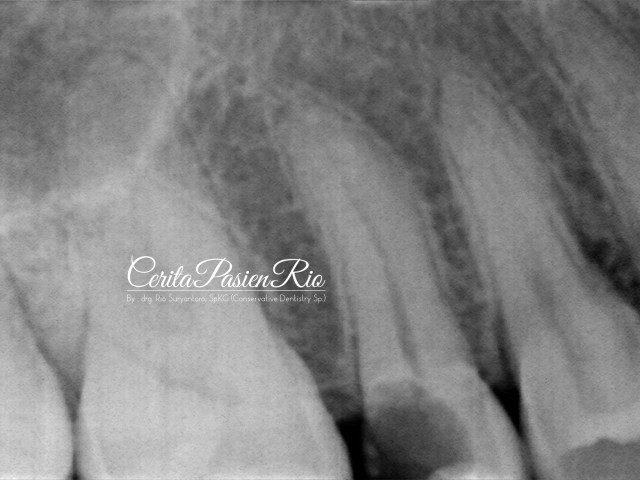

kemudian, saya lakukan foto rontgent dengan keadaan seperti dibawah ini.

gambar 3. foto rontgent dental menunjukkan adanya kehilangan jaringan gigi yang cukup banyak dimulai dari bagian proksimal distal.